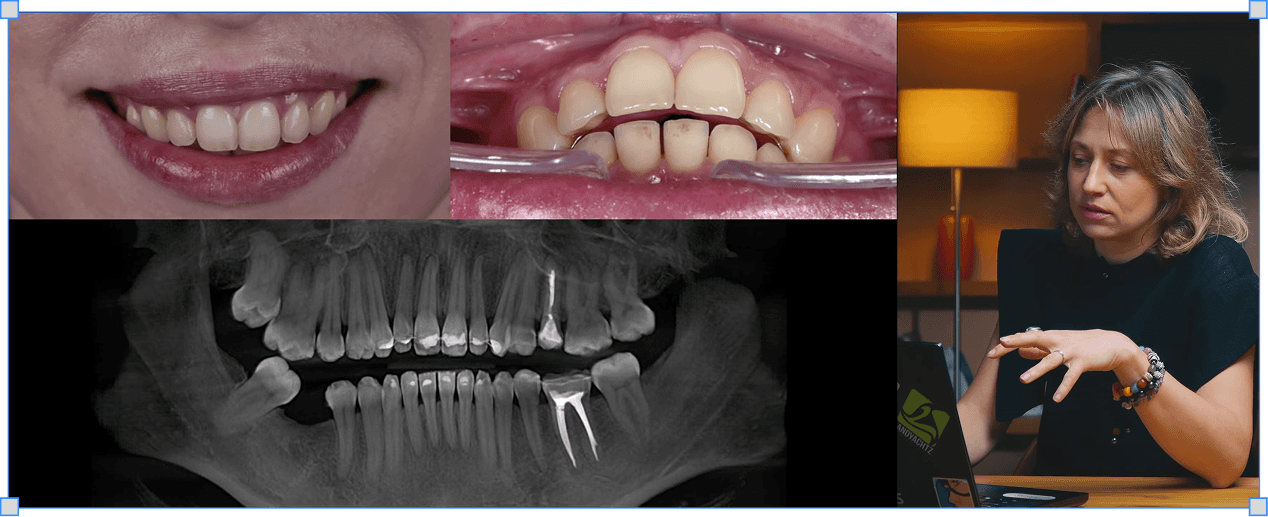

Ірина Гергель

Як планувати ортодонтію від арки ротації і отримувати стабільний прикус

Арка ротації нижньої щелепи, ISC-імпланти для інтрузії, ортогнатична хірургія, калібровка оклюзії